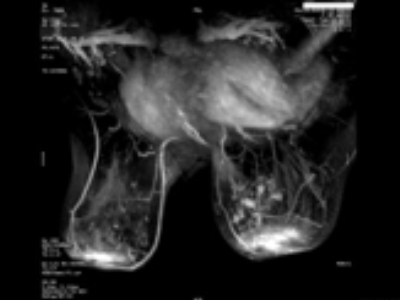

Pacienta P.S. 37 ani- CDIS (tumorectomie cu margini de rezectie pozitive)